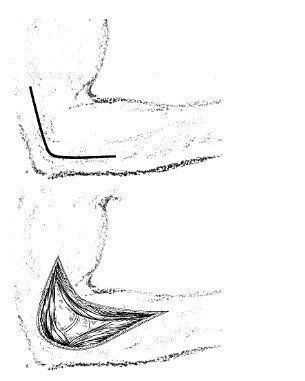

Наружный доступ. Локтевой сустав.

Обнажают верхушку наружного надмыщелка и в параолекраноновой части разреза отыскивают межмышечное пространство между трехглавой мышцей, расположенной сзади, и длинным лучевым разгибателем запястья и плечевой мышцей - спереди. Обнаружив это пространство, проникают в него снизу вверх и таким образом обнажают наружный край плечевой кости. Манипуляции следует производить осторожно, чтобы не повредить лучевой нерв. Общее сухожилие мышц предплечья отделяют от наружного надмыщелка. Затем сухожилие отводят в дистальном направлении, после чего обнажают капсулу сустава (рис. 2).

2. Наружный доступ (а, б) к локтевому суставу.